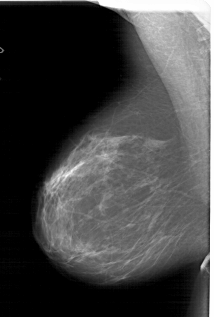

A_1813_1.RIGHT_CC

RIGHT_CC LINES 6481 PIXELS_PER_LINE 4186 BITS_PER_PIXEL 12 RESOLUTION 43.5 OVERLAY